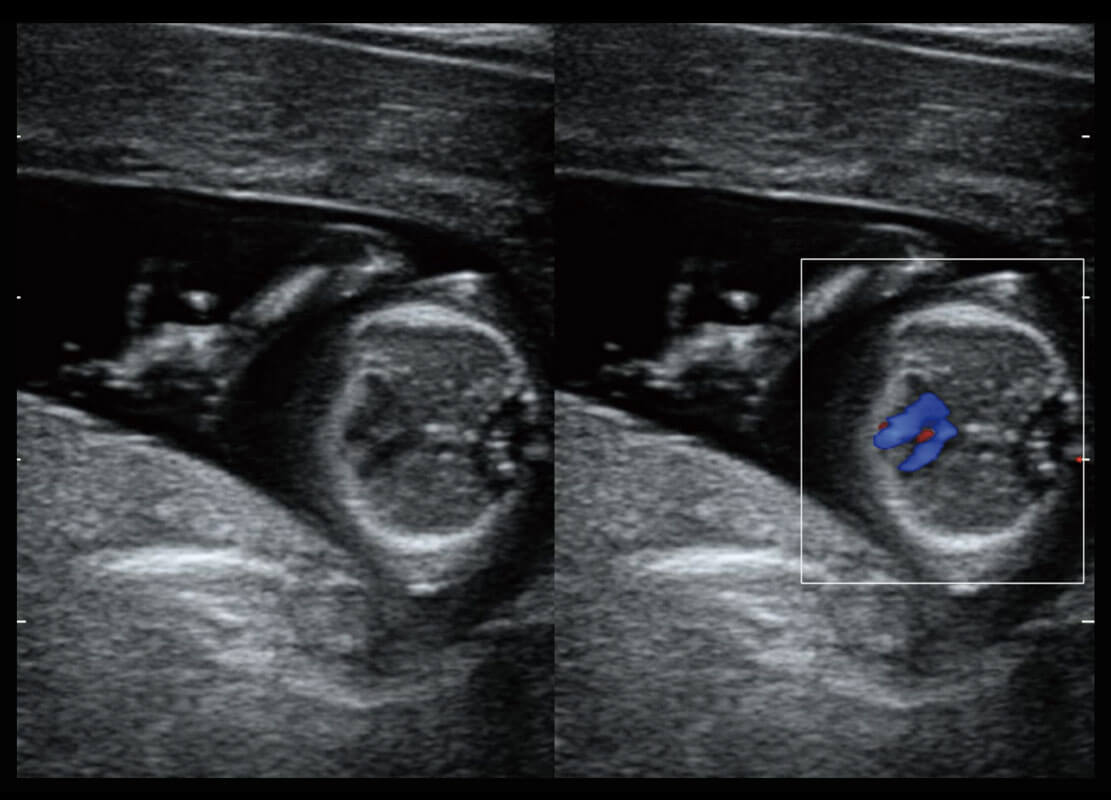

P60搭載一系列胎兒心臟成像技術(shù),實(shí)現(xiàn)精細(xì)的胎兒心臟評(píng)估。

四腔切面

四腔心血流

右室雙出口

胎心容積成像